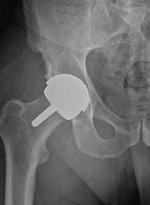

L’arthroplastie ou remplacement de la hanche par du matériel se fait de deux façons. Soit la prothèse totale de hanche (PTH) ( ou Total hip arthroplasty en anglais (THA)), soit le resurfaçage (ou Hip resurfacing arthroplasty  en anglais (HRA)).

La prothèse totale de hanche (PTH) (Total hip arthroplasty – THA) consiste à ôter la tête et le col fémoral et le remplacer par une prothèse. Le cotyle est également remplacé par une cupule synthétique. Dans cette technique, la tête fémorale est beaucoup plus petite que l’originale, le col fémoral d’origine a disparu à la faveur d’un col métallique.

Le resurfaçage (Resurfaçage (Hip resurfacing arthroplasty – HRA) consiste à remplacer le cotyle et la tête. La technique à l’avantage d’avoir une taille plus proche de la tête du fémur d’origine, le col du fémur est préservé et il n’y a donc pas de tige métallique dans le fût du fémur. Par rapport à la PTH classique,  la technique de resurfaçage montre donc un système plus stable (risque de luxation limité), provoquant moins de douleurs au niveau de la cuisse (9) et n’impliquant pas de changement biomécanique du membre inférieur lors de la marche et la course à pied ainsi et une usure limitée (10). Le resurfaçage permet également une proprioception préservée, condition impérative pour un geste technique optimal et un contrôle moteur préservé par rapport à la PTH (11,12).

Prothèse totale de hanche

(chirurgie-orthopédique.info)

Resurfaçage de hanche